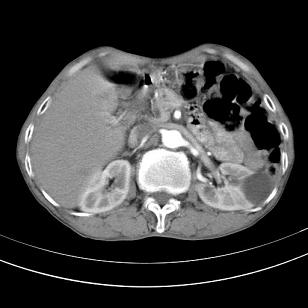

标题: 男,65岁,反复右上腹痛, [打印本页]

标题: 男,65岁,反复右上腹痛,

胃镜提示十二指肠占位